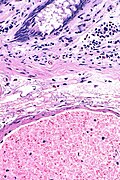

Compatible with angiodysplasia. H&E stain. | |

| LM | dilated vessels in mucosa and submucosa |

- Dilated blood vessels in the mucosa and submucosa.

AD - extremely low mag.

AD - low mag.